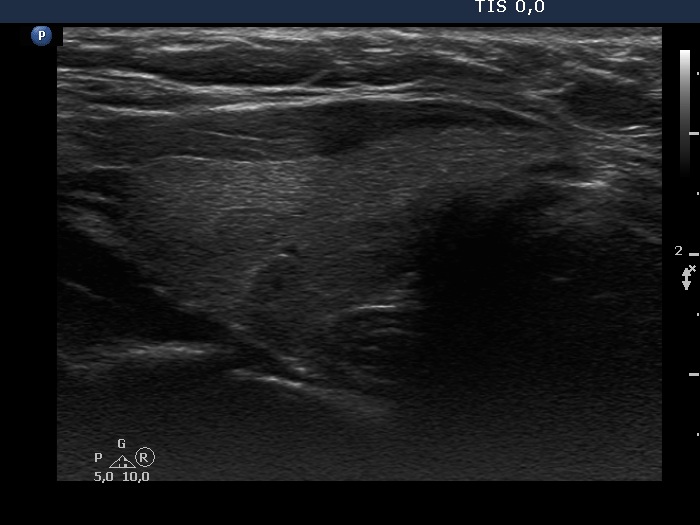

Consecutive patients with the final diagnosis of Hashimoto's thyroiditis - case 19 (1382) (ultrasonographic picture 5)

Left lobe, longitudinal scan.